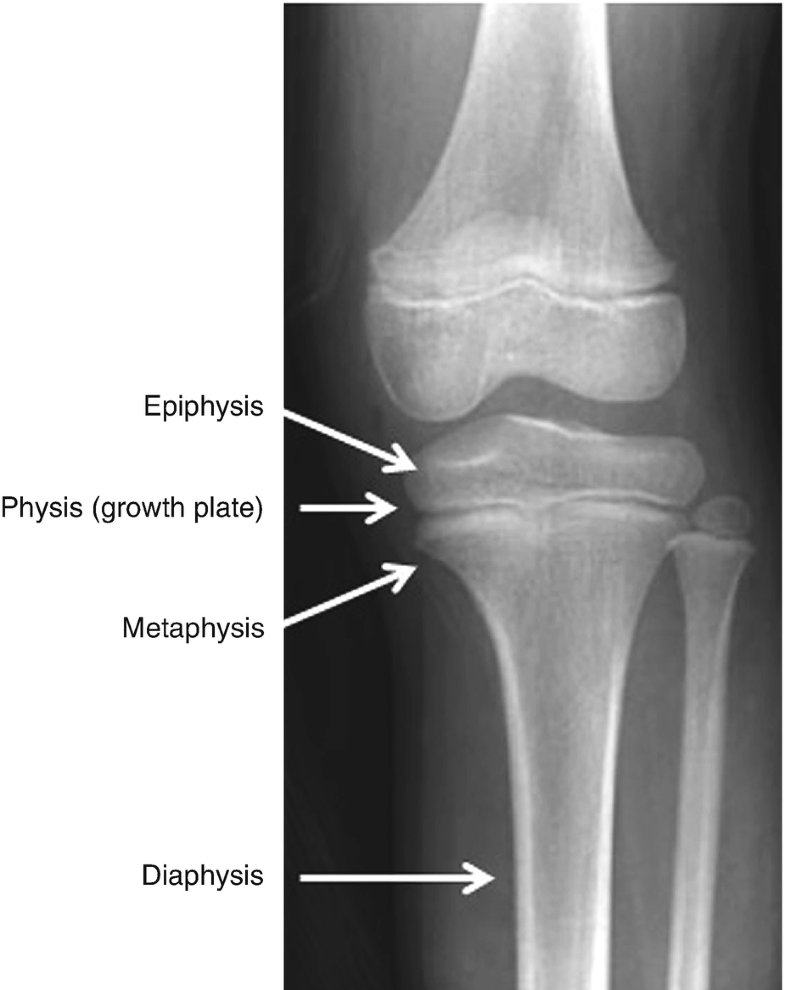

Bone Anatomy Physis. Growth Disturbance In childern due to damage to physis Transverse fractures not dangerous as long it does run through germinal zone Prevented by accurate reduction Epiphysis splitting fractures - asymmetrical growth and angulated bone ends Complete cessation of growth if entire physis is damaged. 86 Surgery also involved a femoral osteochondroplasty including part of the proximal femoral physis with no adverse sequelae noted at 18 months.

Incongruous 50 contact fibrocartilage. 2 1155144 L 2 C Select Answer to see Preferred. Opening in bone Ð passageway for nerves and blood vessels. The zone adjacent to the growth plate on the diaphyseal side is called the metaphysis.